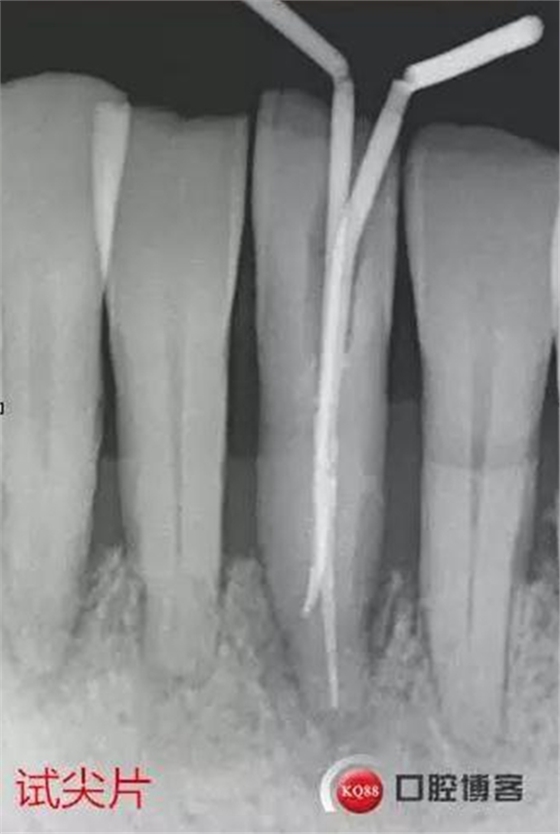

處理:上橡皮障,31開(kāi)髓,測(cè)工作長(zhǎng)度17mm,含氯沖洗液沖洗,機(jī)擴(kuò)至04錐度30#,超聲蕩洗,一次性根充。33-43牙齒鄰接處super bond粘結(jié)固位,行松牙固定。調(diào)合。拍根充術(shù)后片,未達(dá)根尖,懷疑遺漏根管,去除根充物后,繼續(xù)探查根管,找到舌側(cè)根管,測(cè)長(zhǎng)度20mm,時(shí)間原因,未行擴(kuò)根,氫氧化鈣暫封。

圖省事,沒(méi)有拍術(shù)中試尖片,導(dǎo)致術(shù)后重新去除根充物,再次探查,耽誤時(shí)間。

想當(dāng)然的認(rèn)為31單管,忽略了尚有5-10%概率的雙根管情況。

事后再次查看術(shù)前片,可以看到兩個(gè)根管影像,忽略了。